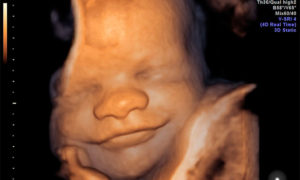

Объемное изображение лица плода на УЗИ

Оба вида УЗИ помогают в получении объемного цветного изображения. Однако, инновацией исследования в 4D-режиме является добавление координаты времени.

- Объемное изображение приближено к реальному, с его помощью можно делать даже определение черт лица младенца.

При проведении Узи 4д при беременности вы увидите объемное и цветное изображение, и даже внешность вашего малыша с малейшими деталями.